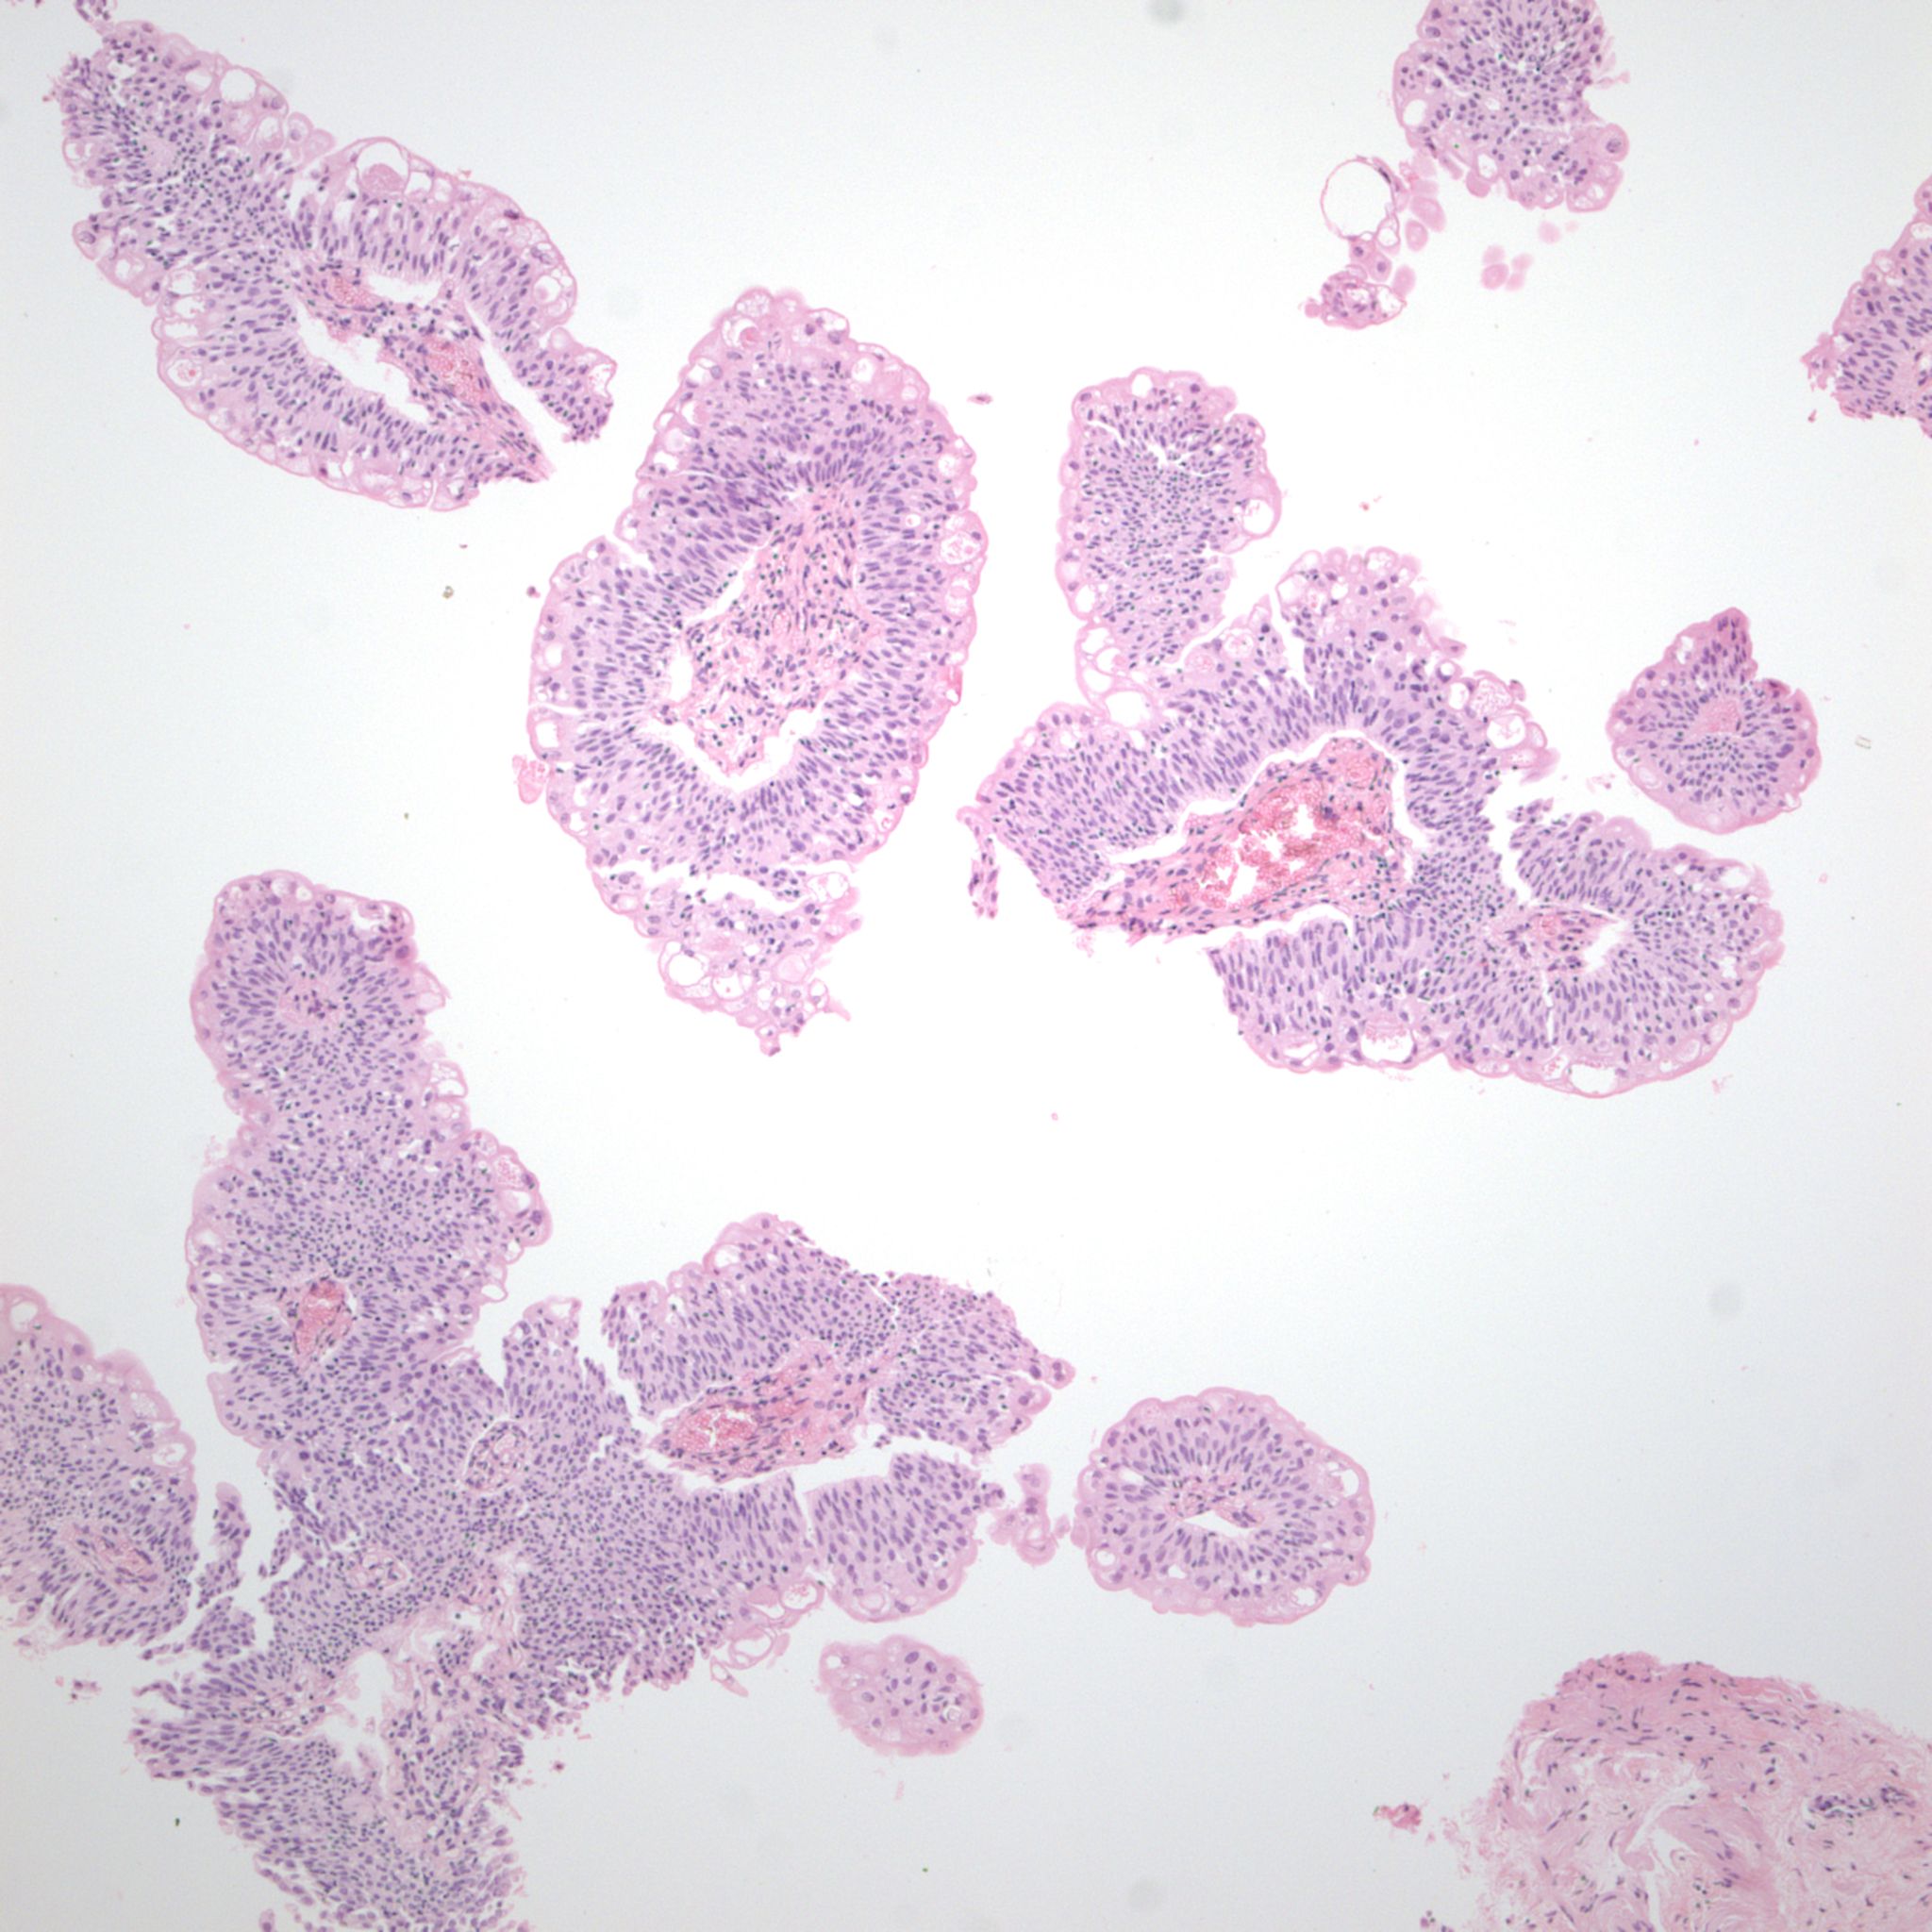

Bladder Papillary Lesions

Case ID: 303